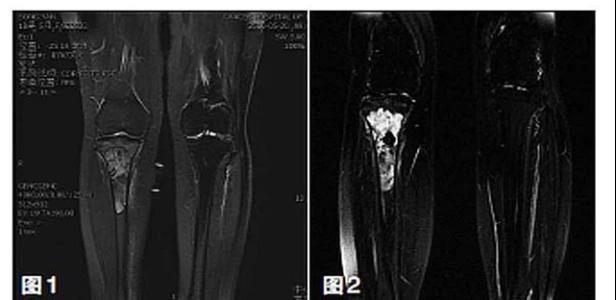

新輔助化療的目的是盡早殺滅遠處微小轉移灶,縮小腫瘤及周圍炎性水腫反應區(qū),以利于后續(xù)的保肢手術;觀察腫瘤對化療的敏感性,為進一步指定個體化的術后化療方案奠定基礎。骨肉瘤新輔助化療下的保肢治療如下圖所示: